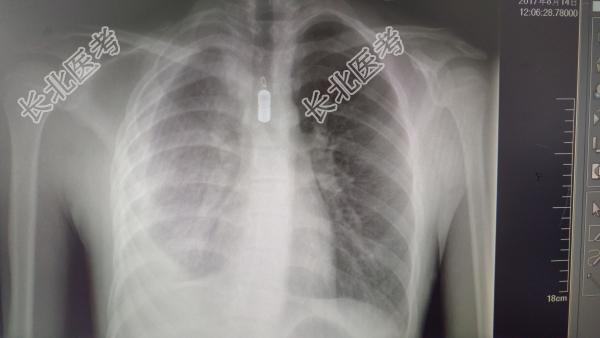

男性,14岁,学生,主诉:发热、腹痛1天。现病史:入院前一天始无诱因出现发热,体温持续在39度,口服退热药物可以维持4小时左右后再次复发,今天晨伴腹痛,口服退热药物(布洛芬)后约5分钟出现呕吐非喷射状态,呕吐物为黄色液体。病来无咳嗽、无腹泻、尿正常,热时有头痛,退后缓解。既往史:半年前诊断为结核性胸膜炎在结核正规治疗中,病情一直稳定。查体:T:38℃,P:110次/分,R:24次/分,BP:100/80/mmHg。发育正常,营养好。全身皮肤粘膜未见黄染及出血点,皮肤凹陷水肿。浅表淋巴结未触及肿大。头颅大小正常,无畸形。头发分布均匀,有光泽。颈软,眼睑无水肿,结膜无充血,巩膜无黄染,双侧瞳孔等大等圆,对光反射及调节反射正常。鼻腔通气可,未见分泌物。耳廓无畸形,外耳道无异常及分泌物。口唇红润,牙龈充血,咽红,双扁桃体无肿大。颈无抵抗,气管居中,甲状腺无肿大,无颈静脉怒张。胸廓对称,无畸形。双肺呼吸音清,右侧呼吸音减弱,偶有干湿啰音,心未见异常。腹部膨隆,上腹部饱满,腹胀,肝脾不大,全腹无压痛及反跳痛,未及包块,肠鸣音活跃。肛门及外生殖器无异常。脊柱四肢无畸形,四肢活动自如,腹壁反射、肱二头肌、肱三头肌、膝腱、跟腱反射正常,病理反射未引出。辅助检查:血常规:WBC6.5X10

/L,N0.55,L0.45;CRP:10g/LMP-AB1:40阴性肝功能、肾功能正常胸片如上超声:肝胆脾胰腺无异常。